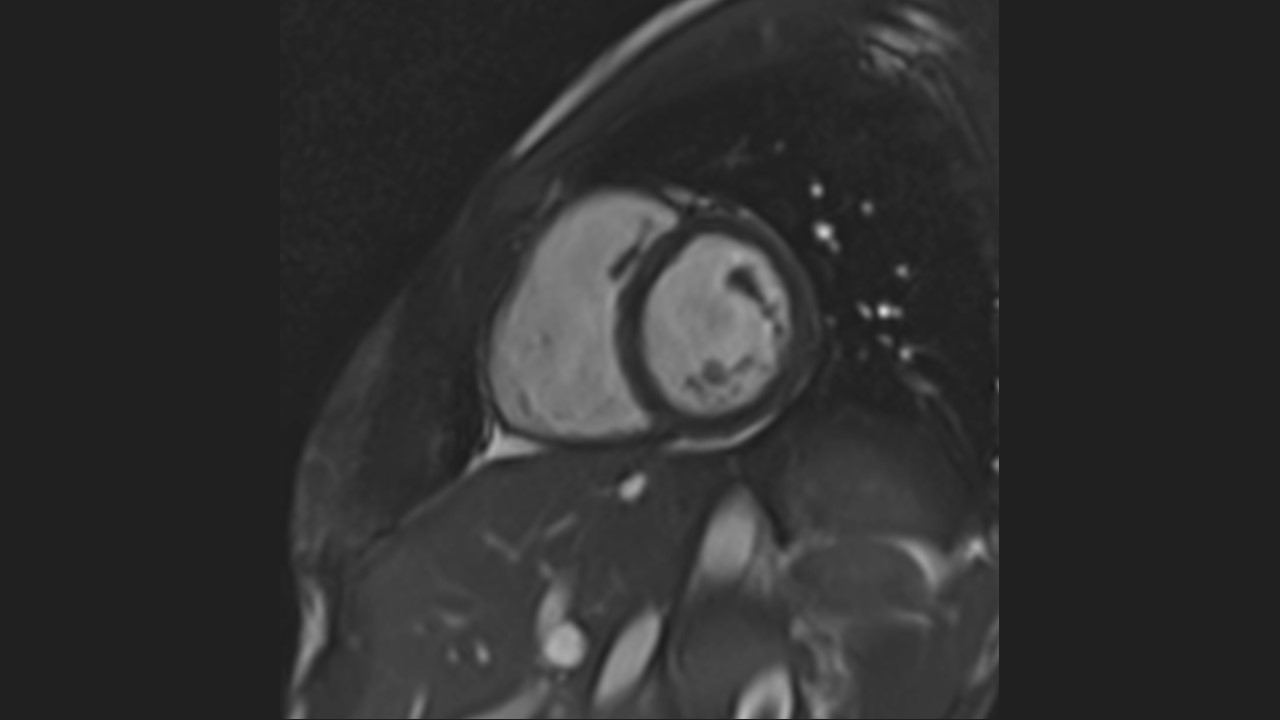

Short Axis Series